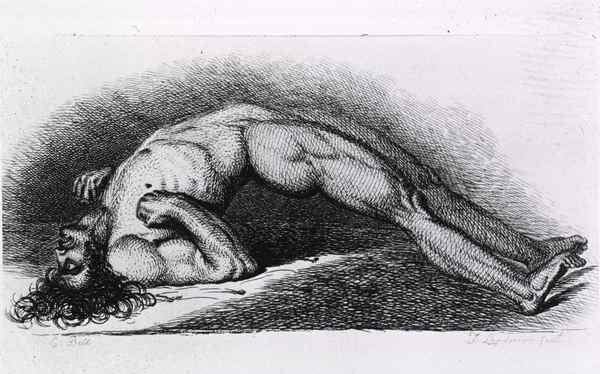

1846年11月18日

波士顿的外科医生Henry Jacob Bigelow,让病人吸入乙醚进行麻醉。这个技术后来运用到各种手术中,从拔牙到截肢。